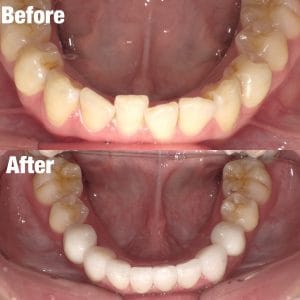

Case029

セラミック矯正の患者様です。

・上下の歯の入れ違い

・正中の歪みと隙間

を主訴にご来院くださいました。

この患者様は若年性歯周炎にかかってしまったため、一生懸命に歯を磨き、口の中は綺麗なのにも関わらず歯茎が下がってしまい、隙間が出来てしまっています。

これは矯正治療で歯の並び方を変えても絶対に無くなりません。

そのため、患者様の主訴を叶えるためにセラミック矯正で治療計画を練りました。

前のクリニックでは「上下一本ずつ抜糸してブリッジで矯正する」という計画だったようですが、

・患者様が非抜歯を希望されていること

・歯を抜かなくても綺麗に並べられそうだったこと

を理由に、当院では上は抜かずにセラミック。下は形態修正だけで対応しました。

この方針変更だけでもお値段も安く、また侵襲(ダメージ)を少なくすることができました。

治療の結果、最低限の侵襲で、見違えるほど綺麗な口元に治療することができ、患者様もとても喜んでくださいました。

【主訴】

・上下で入れ違っている前から2本目の歯のすれ違いを治したい。

・清潔感のある白さで明るい綺麗な口元にしたい

・歯の隙間を無くしたい

【ご要望、ご状況】

・歯を抜かずに治したい

・前医では上下1本ずつ抜歯をして、ブリッジで上3本、下3本の計6本を治すことを提案された。

【今回の治療法】

・右上の犬歯から左の前歯までの計4本をジルコニアセラミックで治療

・色は自分の歯よりやや白いくらいでホワイトニングをしてもしなくても大丈夫なくらいの白さ

・歯は抜かない

・右下の歯は形態修正だけで対応

・歯茎のラインを歯肉整形術で整える